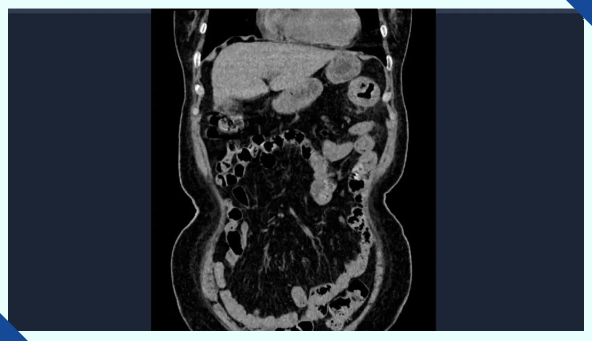

在进一步的全腹部CT检查中,医生发现李阿姨脾区存在占位性病变。按照常规经验,脾区肠道出现问题往往会伴随便血症状,但李阿姨却坚称自己从未出现过这种情况。消化内科的吕后宁主任没有轻易下结论,而是耐心地追问起她的排便情况。这时,李阿姨才想起,自己最近一段时间大便颜色发黑,但一直以为是长期喝中药导致的,根本没往肠道疾病上想。正是这个被忽视的“黑色信号”,让病情一拖再拖,直到贫血症状严重才引起重视。